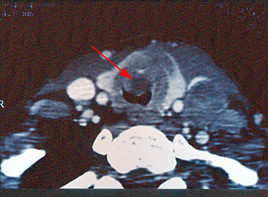

Le Scanner

Il a peu d’intérêt dans le « nodule simple » mais trouve sa place dans le bilan d’extension des cancer et dans les volumineux nodules compressifs.

Scanner : Cancer anaplasique de la thyroïde avec extension endo-trachéale (flèche)